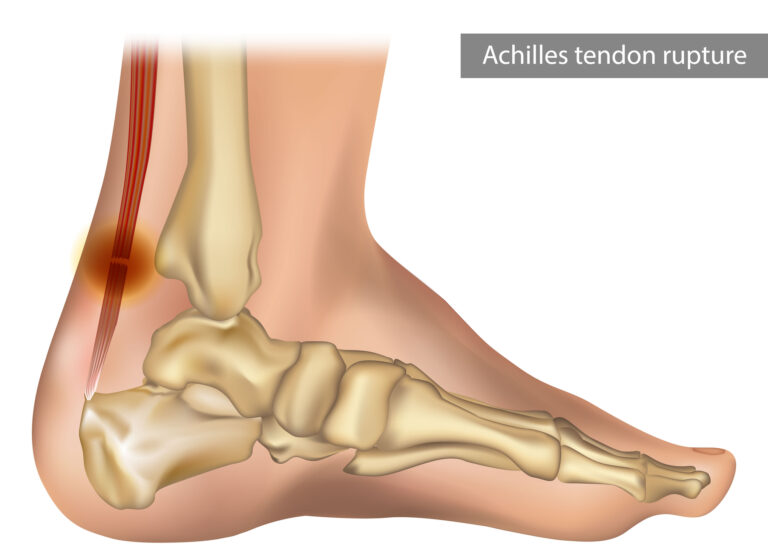

Haliburton hral už so zraneným lýtkom, keď v rozhodujúcom zápase proti Oklahome utrpel roztrhnutie achilovky. V pondelok podstúpil operáciu a hrozí, že vynechá celú sezónu 2025/2026. V play-off utrpeli rovnaké zranenie aj Jayson Tatum z Bostonu a Damian Lillard z Milwaukee.

„Či to súvisí so zraneniami lýtka, zatiaľ nevieme, ale berieme to veľmi vážne,“ dodal Silver.